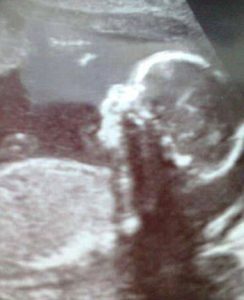

وكان الطفل “أولى تريزيس” والذى يبلغ من العمر 21 شهراً، يعانى من حالة نادرة للغاية تسمى “التهاب الدماغ” والتى تسببت له فى فجوة داخل جمجمته ونمو جزء من دماغه داخل أنفه، لذلك أطلقت عليه والدته اسم “بينوكيو”.

وقالت أم الطفل “بينوكيو” إن هناك العديد من الأشخاص قالوا إن قرار بقاء الطفل عند إجراء السونار خلال فترة الحمل خاطئ جداً، فى حين سخر البعض منه، ووصفه بأنه طفل “قبيح”.